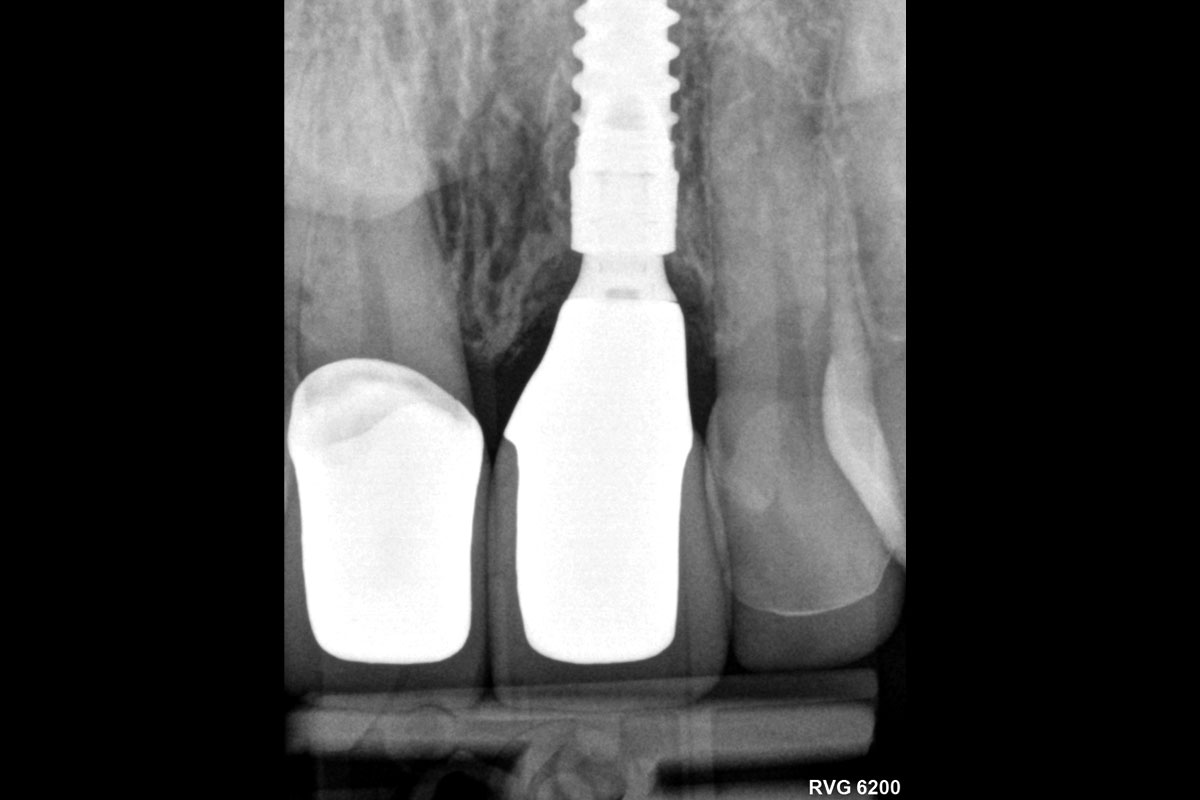

28/30 - Radiological control after surgeryExcellent aesthetic result of buccal augmentation with mucoderm® and maxgraft® after immediate implant placement - 3-years follow-up - Dr. A. Puišys